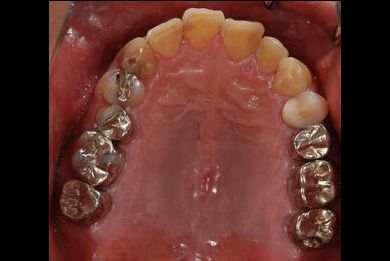

インプラントの症例写真 IMPLANT

インプラント治療+セラミック治療+歯肉歯槽骨整形術

| 治療内容 | インプラント2本、メタルボンドセラミッククラウン9本(メタルボンド用土台6本)、ハイブリッドセラミッククラウン2本(セラミック用土台2本)、ハイブリッドセラミックインレー5本、歯肉歯槽骨整形術 | ||||||||||||||||||||||||||||||||